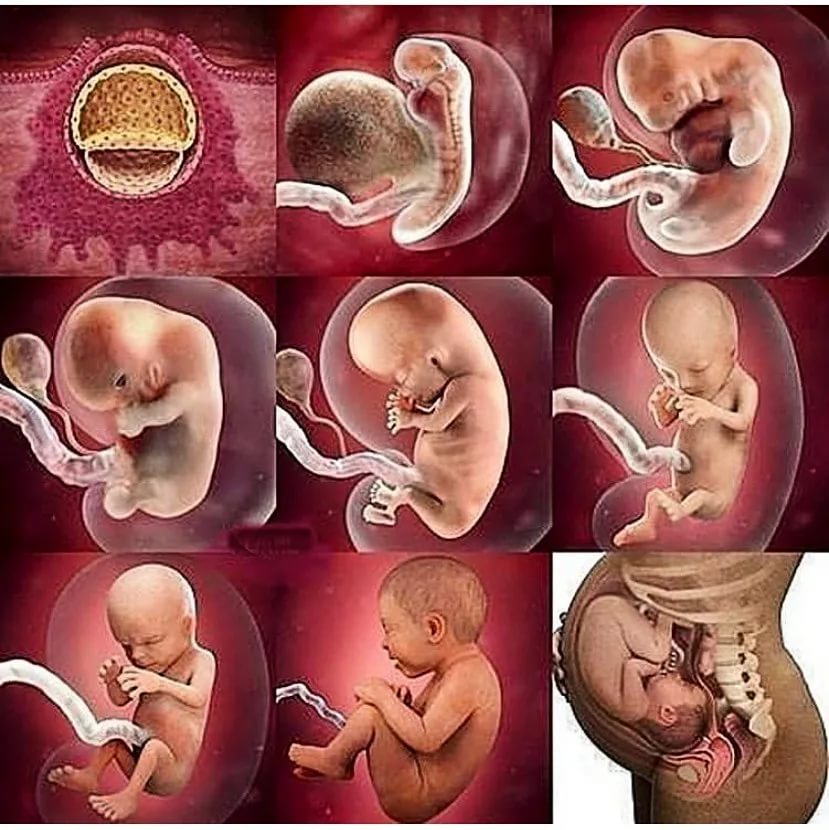

Загадочные образы животных в утробе матери

Раздел: Другие животные